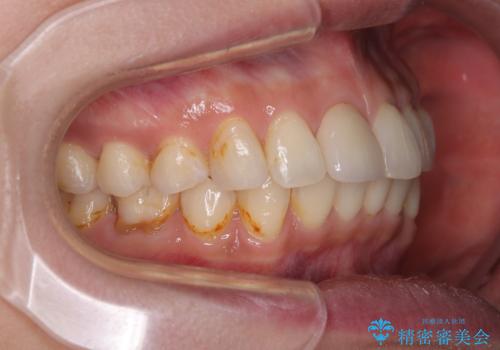

デコボコと乳歯の欠損 ワイヤー矯正とインプラント補綴治療

- 全体的なデコボコと左下乳歯部の欠損を気にして来院された患者様です。

乳歯が抜け落ちた後の後続永久歯が欠損しているため、スペースが残っておりました。

口元の突出感を気にしているのであれば欠損スペースを利用して抜歯矯正を行うことも可能ですが、横顔の印象はスッキリとしている状態であったため、矯正治療でスペースを閉じきることは不可能と判断し、インプラントによる補綴治療を行うこととしました。

第二小臼歯の欠損によるが乳歯残存や欠損が多く、この乳歯は後続永久歯に比べて幅が非常に大きいため、教聖地料によるスペースクローズが難しいことが一般的です。